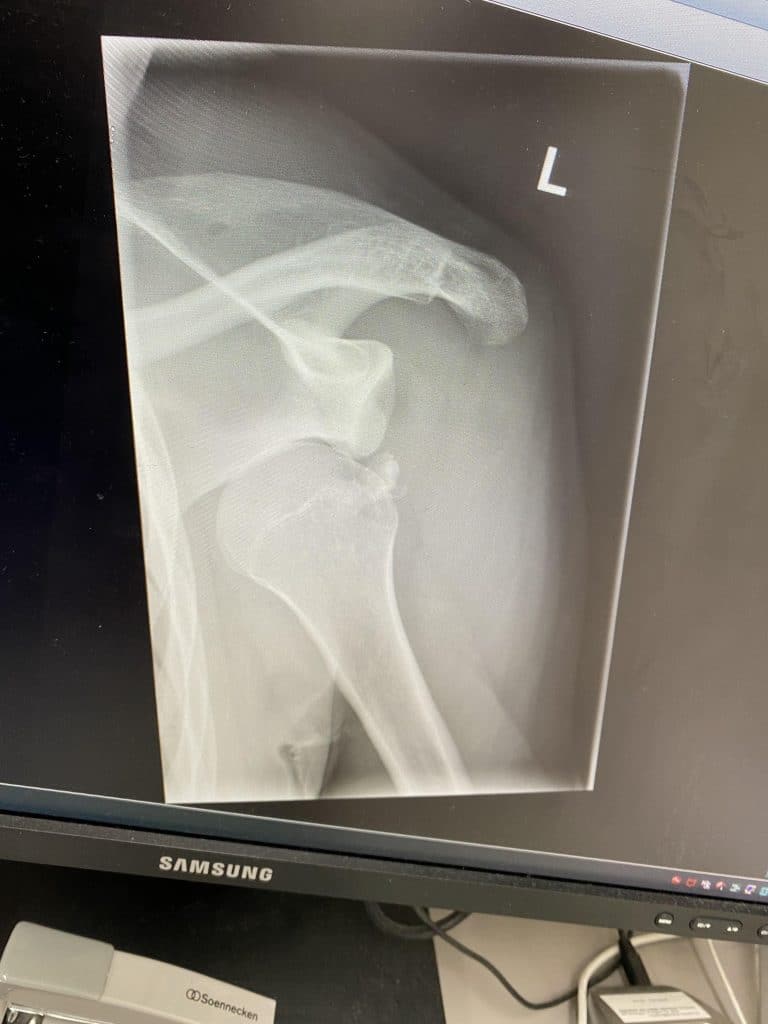

Getting off a chairlift is way sketchier than people admit. Once the snowboarder in front of me decided to sort of ollie off the ramp instead of just riding it out. His nose dug in, he went flying and his shoulder popped out before his day had even started. The rest of us had to shuffle around him and attempt to escort him down the hill. Took an hour.